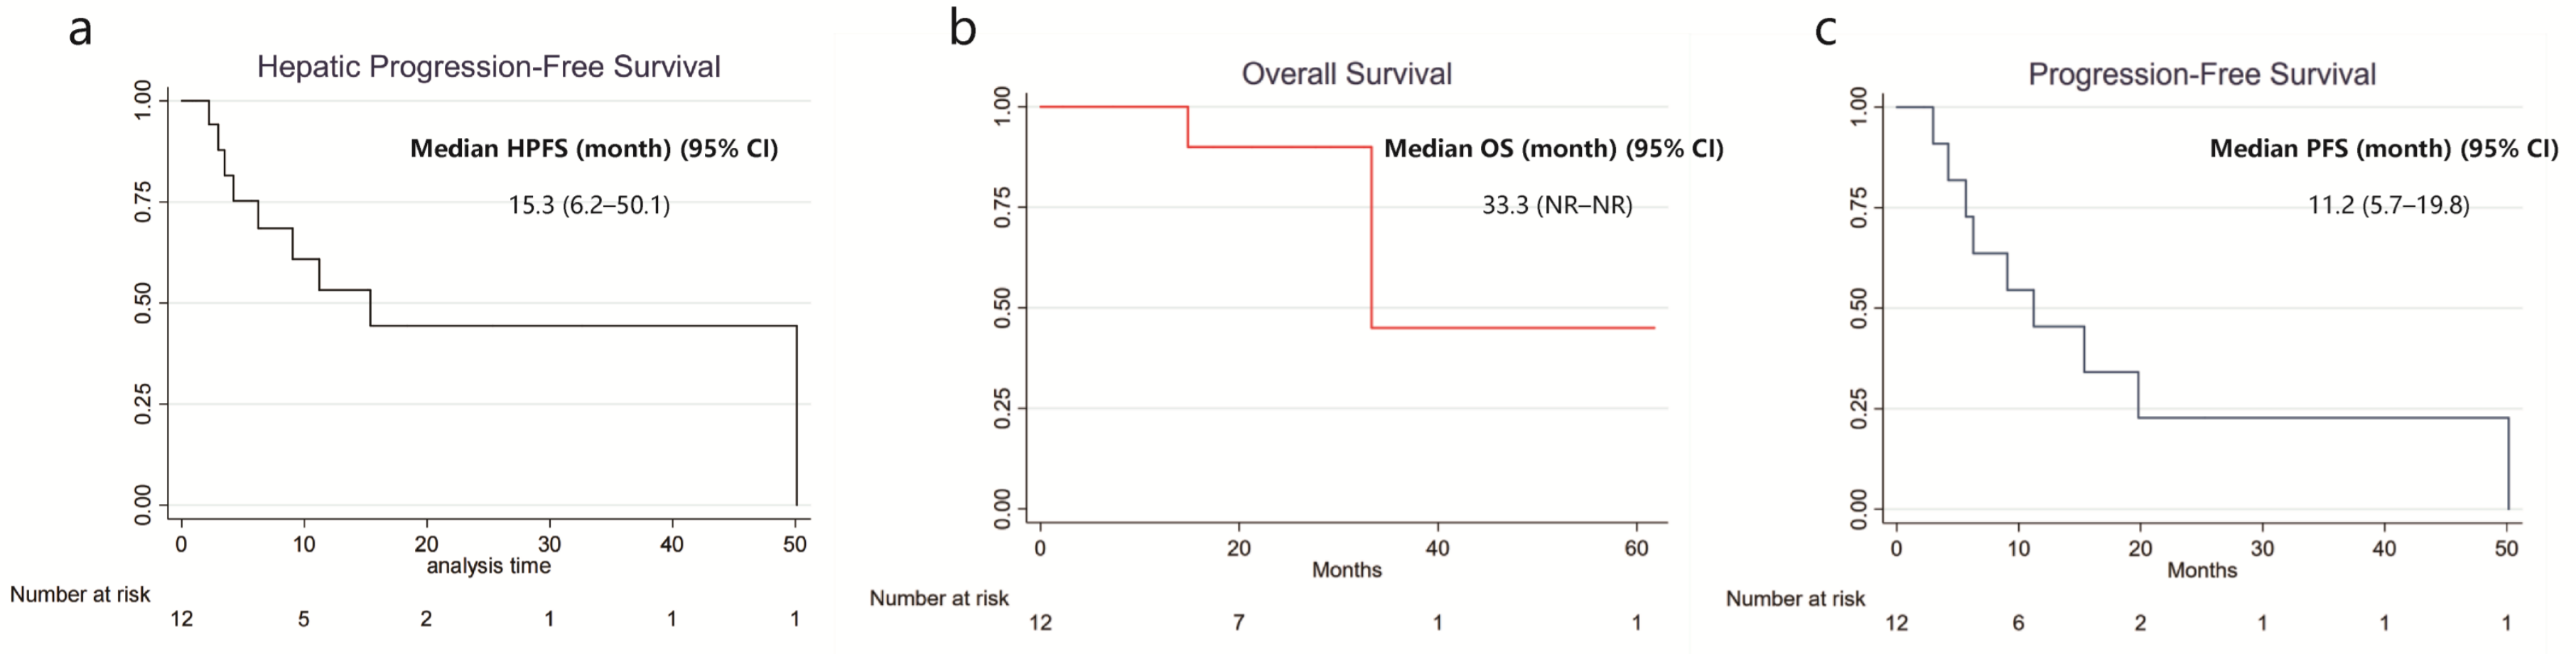

3.1.3. Clinical Outcomes

3.2.3. Survival Outcomes